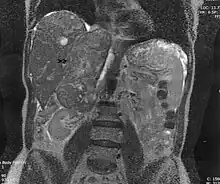

Son dépistage s'avère difficile et l'IRM semblant être le meilleur examen pour le distinguer d'un simple fibrome[5] et la biopsie de l'endomètre semble d'une sensibilité limitée[6].